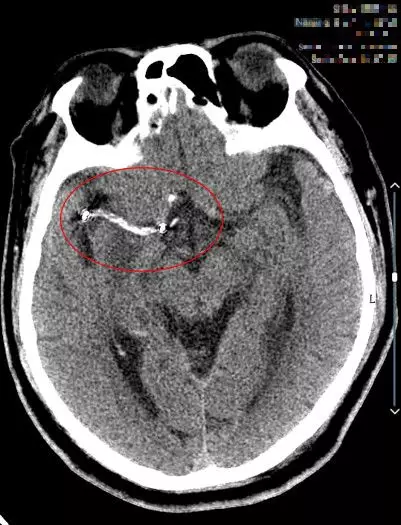

9:40分左右,患者逐渐开始出现烦躁、嗜睡,查体:言语不清,左侧肢体肌力0-1级,急查头颅MRI+MRA+颈部MRA阅片见,右侧基底节区急性脑梗死,右侧大脑中动脉闭塞。

复查头颅CT(09:48分)

术后24小时内复查头颅CT(08-04日 14:38分)